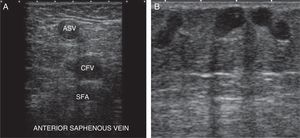

We will begin the study at the level of the sapheno-femoral junction in B-mode (Mickey Mouse sign) (Fig. 8B).

N2 or secondary network: between both fasciae (sign of the eye) (Fig. 2). The superficial venous system is located here and it is made up of the internal saphenous vein (ISV), the external saphenous vein (ESV), and their anatomical variants (anterior saphenous and Giacomini veins) (Fig. 3A).

The ISV is the most important trunk of the superficial venous system. It originates in the anterior side of the internal malleolus and it runs from the leg to the groin through the inner side of the thigh, to drain through its arch into the DVS (common femoral vein, CFV).